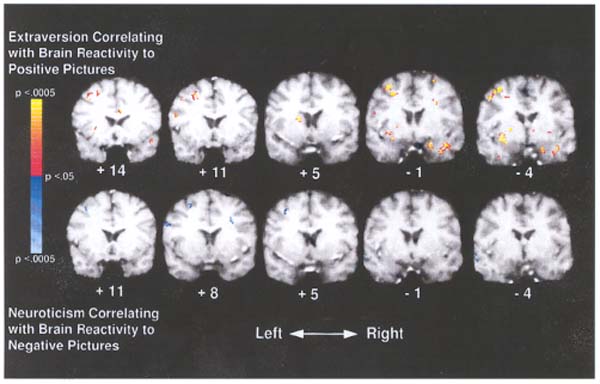

Wie jeder weiß, reagieren extravertierte, introvertierte und neurotische Menschen anders auf ein und dieselben Reize aus ihrem Umfeld. Vollkommen neu ist allerdings die Tatsache, dass bereits vor ihren allen erkennbaren Reaktionen – aufgrund ihrer unterschiedlichen Bewertung, Beurteilung und neurobiologischen Weiterverarbeitung – ganz bestimmte Hirnregionen bei ihnen aktiver oder weniger aktiv sind. Wie die folgenden 10 fMRI-Scans (Siehe unten: coronale Aufnahmen, Durchsicht von vorn.) von emotionalen Reaktionen auf 40 angenehme oder unangenehme Bilder zeigen, leuchten sie beim Betrachten der Bilder von Mensch zu Mensch unterschiedlich hell auf.

Die obere Reihe zeigt rot gefärbte Hirnregionen, deren Reaktionen auf 20 angenehme Bilder wie glückliche Paare, Puppen, Sonnenuntergänge auf dem Land, Eiscreme oder Süßigkeiten, mit der Wesensart Extravertiertheit zusammenhängen. Extravertierte (und damit in der Regel glückliche) Menschen hatten als Reaktion auf das Betrachten dieser Bilder stärkere Aktivitätsmuster als introvertierte Menschen in den folgenden Hirnregionen: Amygdala (Aufnahme – 1), caudate Nucleus (Aufnahme + 5), Putamen (nicht dargestellt in der oberen Reihe) und mittlere vordere Hirnwindung (Aufnahme + 14).

Die untere Reihe zeigt blau gefärbte Hirnregionen, deren Reaktionen auf 20 unangenehme Bilder wie weinende oder wütende Menschen, Spinnen, Gewehre oder ein Friedhof, mit der Wesensart Neurotizismus zusammenhängen. Neurotische (und damit in der Regel unglückliche) Menschen hatten als Reaktion auf diese Bilder stärkere Aktivitätsmuster als gefühlsmäßig ausgeglichene, gelassene Menschen in den folgenden Hirnregionen: Mittleres Vorderhirn (Aufnahme + 5) und mittlere Schläfenlappen-Hirnwindung (Aufnahme – 4)11).

Copyright © 2001 by Turhan Canli, Stanford University / USA

(Grafik links): Sehr enge, geradlinig ansteigende Zusammenhänge zwischen der Wesensart Extravertiertheit (NEO Scores) und dem Reagieren dieser Hirnregionen auf angenehme Bilder (z-Scores). Einfacher ausgedrückt: Je extravertierter jemand ist, desto stärker reagieren diese Hirnregionen auf angenehme Bilder. (Grafik rechts): Sehr enge, geradlinig abnehmende Zusammenhänge zwischen der Wesensart Neurotizismus (NEO Scores) und dem Reagieren dieser Hirnregionen auf unangenehme Bilder (z-Scores)11).

Ansicht von vorn: Neurotische und extravertierte Gehirne